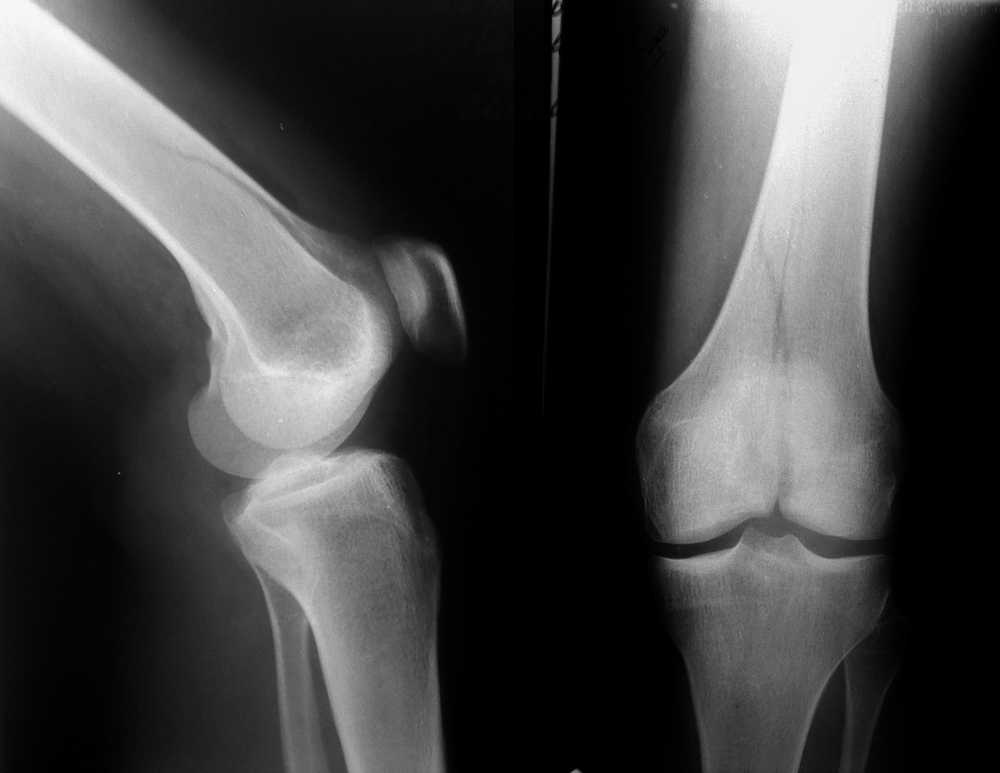

Межмыщелковый перелом бедра

Перелом медиального мыщелка правой бедренной кости, по классификации Мюллера - 33-В2.1

Женщина, 24 года, травма в быту, при падении с лестницы на согнутое колено.

Кожные покровы в хорошем состоянии, гемартроз умеренный, повреждения крестообразных связок пока не видно.

По снимкам имхо не очень понятно, где же на самом деле заканчивается линия перелома.

Можно засунуть хорошую конструкцию, а потом быть "приятно удивленными" неожиданным продолжением линии перелома.

Внутрисуставной, простой перелом у молодой пациентки с хорошим качеством кости требует: во-первых, анатомичной репозиции, что в данном случае при небольшом смещении не должно вызвать затруднений, во-вторых, межфрагментарной компресии посредством стягивающих винтов для достижения абсолютной стабильности. Пластина, которая бы эффективно дополняла бы стягивание винтами, как нейтрализующая или противоскользящая, должна быть установлена по медиальной воверхности, что в данном случае на бедре малоприемлимо ввиду анатамических особенностей и трудности доступа. Пластина клинковая, или мыщелковая, или DCS, установленные снаружи, не будет выполнять этой функции. Штифты вообще не показаны при переломах 33.В..

Мы бы ограничились двумя стягиваюшими спонгиозными винтами на уровне мыщелков (губчатой кости) и одним стягивающим с кортикальной резьбой на диафизе... Но сначала анатомичная репозиция. Никаких внешних иммобилизаций, ранние движения, нагрузка недель через 6